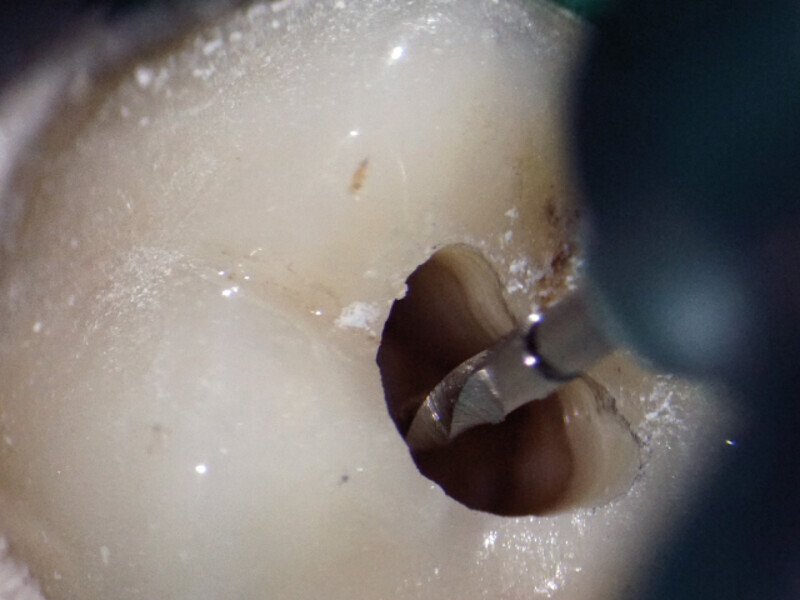

Endodontické ošetření – případová studie